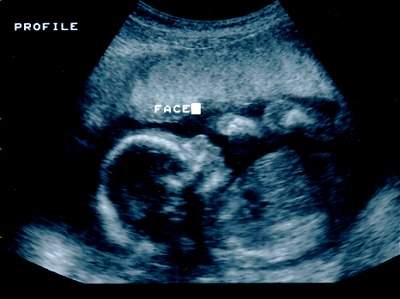

ستحتاجين لفحوصات أشعة للتأكد من أن حجم الجنين و هيئته ليست غريبة أو شاذة. ان هذه الأشعة و التي تصور مابداخل الرحم هي فرصة اللفريق الطبي لفحص رأس و أطراف و أعضاء الجنين.

متعي ناظريك برؤيته في الاسبوع العشرين